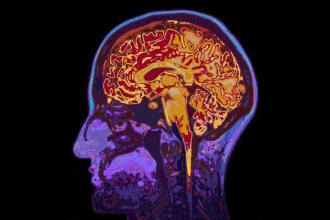

据国外媒体报道,长期以来,人们一直认为腹部脂肪会对心脏特别不利,但近日一项新研究指出,肥胖的肚子还可能对大脑有害。

这项来自英国拉夫堡大学的研究发现,与健康体重的人相比,身体肥胖且腰臀比(腰围与臀围的比例,可以作为衡量腹部脂肪的指标)较高的人具有略低的平均脑体积。具体而言,腹部脂肪与较小的大脑灰质体积存在关联。灰质是中枢神经系统的重要组成部分,由神经元、神经胶质细胞和微血管组成。

较低的大脑体积,或者脑萎缩,可能会引起记忆力下降和痴呆的风险增加。这项新研究的结果发表在1月9日的《神经病学》(Neurology)期刊上,指出肥胖(通过身高体重指数来测量)和较高的腰臀比可能是大脑萎缩的风险因子之一。

该研究发现,相比BMI较高(但腰臀比不高)和健康体重的人,BMI和腰臀比都较高的人具有最小的大脑体积。具体而言,BMI和腰臀比都比较高的人平均灰质体积为786立方厘米,而BMI较高但腰臀比正常的人则为793立方厘米,健康体重的人是798立方厘米。在研究人员考虑了其他影响大脑体积的因素,包括年龄、吸烟和高血压等之后,研究结果依然成立。

研究人员表示,尽管该研究并未分析内脏脂肪与大脑萎缩之间关联的潜在机制,但有一种假说认为,这类脂肪可能会产生在脑萎缩中起作用的刺激物质。纽约林诺克斯山医院(Lenox Hill Hospital)的Gayatri Devi并未参与该研究,她对研究结果表示认同。“大脑灰质缩小……似乎与肥胖和内脏脂肪的增加有关,”她说,“这一切都表明良好的整体健康状况对于保持大脑健康至关重要。”